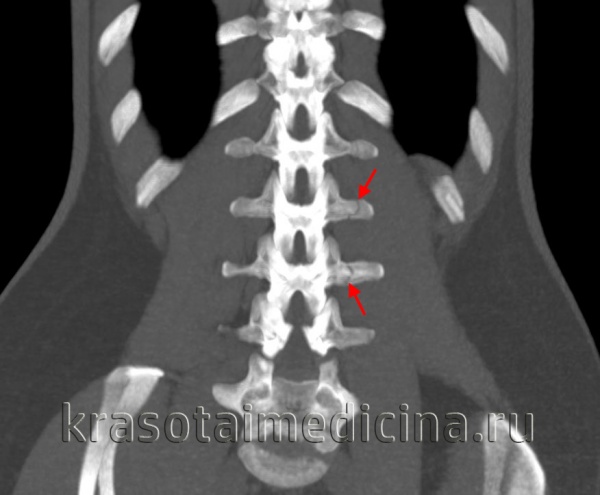

• Смещение задней покровной пластинки в спинномозговой канал, лучше всего определяемое в Т2-режиме:

о Аксиальные Т2-ВИ используются для оценки выраженности компрессии нервных образований

• Признаки контузии спинного мозга также лучше всего видны на аксиальных Т2-ВИ:

о Усиление интенсивности сигнала спинного мозга

(Слева) КТ, сагиттальный срез: оскольчатый взрывной перелом тела L4 позвонка со смещением фрагмента кпереди и выраженным смещением одного из фрагментов кзади.

(Справа) На Т1 -ВИ отмечается снижение интенсивности сигнала тела L4 позвонка на фоне его перелома. Смещенные кзади фрагменты сдавливают вентральную поверхность дурального мешка, имеет место значительных размеров эпидуральная гематома. Таким образом, выраженная компрессия дурального мешка связана со смещением фрагментов в спинномозговой канал и эпидуральной гематомой.